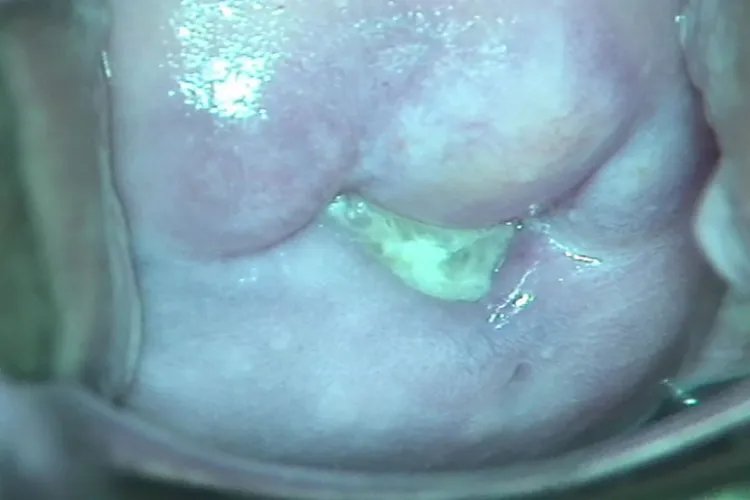

外阴阴道假丝酵母菌病外阴阴道假丝酵母菌病患者的白带呈豆腐渣样或凝乳状,白色稠厚、略带异味,部分患者白带夹有血丝,阴道黏膜充血、红肿,甚至有溃疡形成,患者可伴有尿频、尿急、尿痛及接触痛等症状。